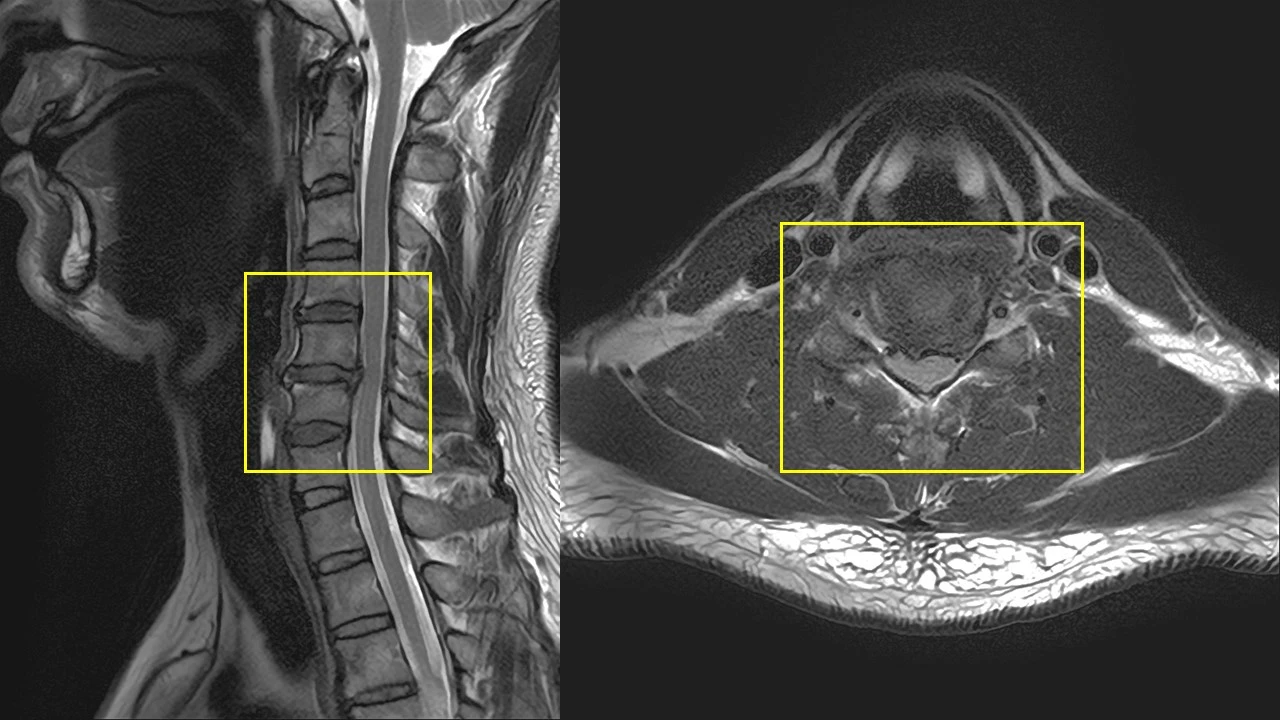

워낙 척추 MRI를 많이 봐왔기에 어느 정도 판독은 할 수 있는 터라,

집에서 CD에 담긴 사진을 횡단면, 종단면 맞춰가며 분석했다.

아, 5~6번 사이 디스크가 터져서 밀려 나와있는 상태였다..

목디스크, 말로만 듣던 것이 정말 눈으로 확인된 순간이었다.